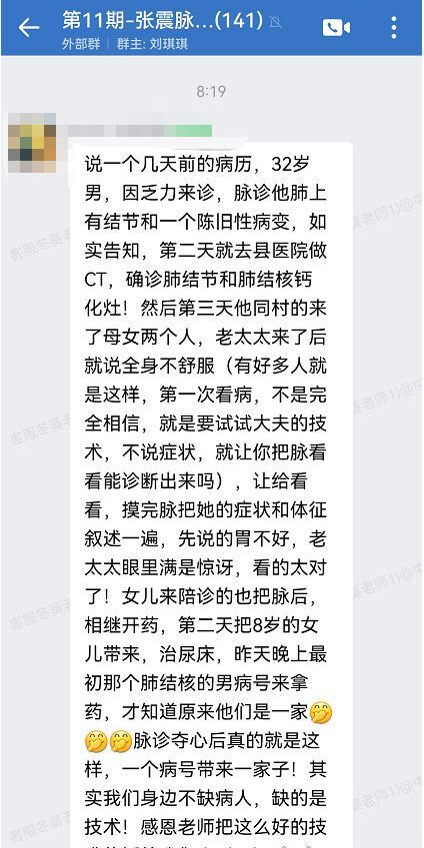

32岁的王先生就是这样的有福报、有运气之人。

某天,王先生感觉全身乏力,长辈推荐他去看一看中医,调理下身体。

几经打探,王先生来到当地一家患者口碑比较好的医馆,给他看诊的是一名姓吴的大夫。

谁承想,吴大夫的几句话让王先生差点骂出脏话!

“您的肺上不仅有结节,还有陈旧性病变。”

第二天一大早,王先生不情不愿的来到县医院体检中心,还特意做了肺部的CT。

"王先生,CT显示,您的肺中有结节,且有肺结节钙化灶。"

王先生拿着片子沉默了半分钟,才说出一句话:"真他妈神了!"

转眼到了第二天,医馆里来了母女俩:一位老太太,一位中年女性。

还没等吴大夫问,老太太开口了:大夫,我浑身不舒服啊,您能治吗?

吴大夫对助理淡淡的一笑,他知道:很多人对中医,尤其是对*次看诊的中医,总是不完全相信,甚至持有怀疑态度。

老太太不说出自己的病症,就是要试试他的医术如何,是否能通过把脉诊断出她的问题。

吴大夫跟往常一样给她仔仔细细的号脉:您的胃不好,是老毛病了。

只这一句话,老太太就满脸的惊讶,被吴大夫成功“夺心”。

接着,吴大夫又详细的给她描述了一遍症状和体质体征,老太太已经从头到尾信服了他的医术!

陪同老太太来看诊的女儿——林女士,也听的目瞪口呆,随即让吴大夫给诊脉。

毫不意外,诊脉结果同样是无比精准、无比让人信服的。

随后,母女两人带着吴大夫开的药,安心的回家了。

第三天,林女士又带着她的女儿走进了医馆:

“吴大夫,孩子8岁了,还总是尿床,麻烦您看看。”

到了晚上,林女士竟然又双叒来了!

这次跟林女士一同来的,竟然是*天被吴大夫确诊肺结核的王先生!

吴大夫这才明白,原来他们都是一家人。

一个病人,带来一家人。这就是中医脉诊夺心的力量。

「吴大夫阐述一家四口看诊经过」